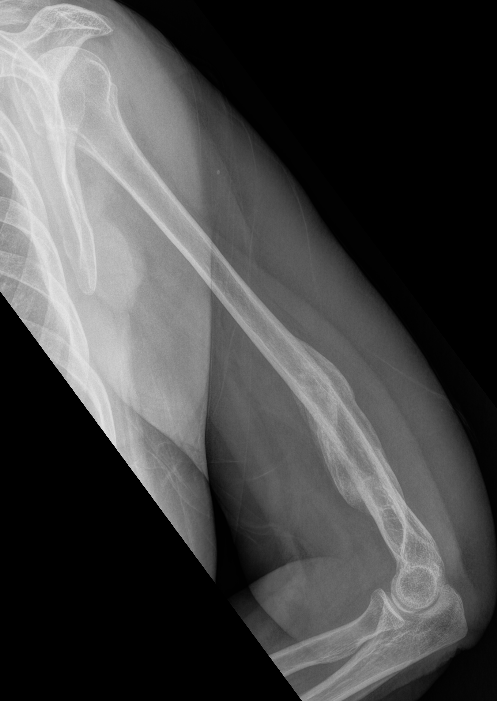

Nonunion in a proximal humerus shaft fracture treated nonoperatively